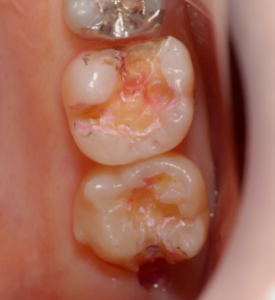

症例1

治療前の状態です。金属の詰め物が入っています。

金属を除去すると茶色の虫歯があるのがわかります。

症例2

治療前です。

茶色の虫歯が見えます。

齲蝕検知液で染め出します。

赤く染まった部分が虫歯です。

完全に取り除きました。